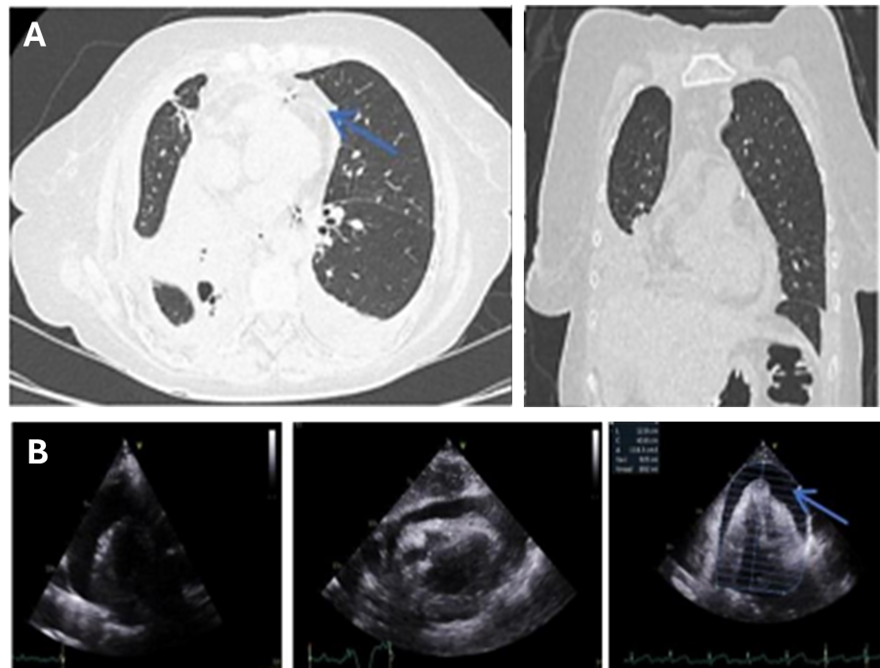

The Cardiac pathophysiology of Covid-19

Hubert Daisley, Oneka Acco, Haille Joseph, Johann Daisley, Martina Daisley